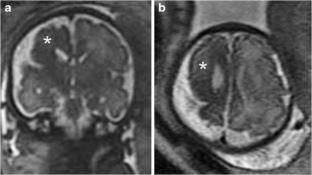

Pre- and postnatal imaging of early cerebral damage in Sturge-Weber syndrome

A case of prenatal diagnosis of Sturge-Weber syndrome associated with polymicrogyria is reported. The diagnosis was based on a unique association with unilateral hemispheric gyriform calcification, focal hemispheric atrophy and white matter changes on prenatal imaging including ultrasound and MRI. Polymicrogyria, which is exceptionally associated with Sturge-Weber syndrome, is suggestive of and reinforces the hypothesis of early impairment of the cerebral microvasculature related to leptomeningeal angioma, which may lead to abnormal cerebral development as early as the second trimester of pregnancy.

Fig. 2

Fig. 3